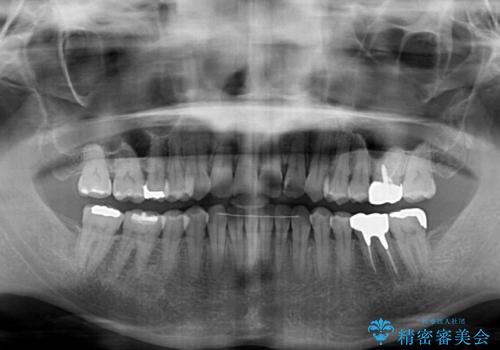

舌側転位している側切歯特有の、切縁の位置が不揃いであったり、根元が内側に引っ込んだ状態であったりという、インビザライン独特の仕上がりになることなく、きれいに整った歯列とすることができました。